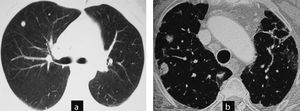

Case 4 (Fig. 3)This patient was a 66-year-old male, diagnosed with RA for 9 years, RF positive and an ex-smoker. A year ago he was diagnosed with interstitial lung disease with respiratory symptoms, moderate dyspnea and mild restrictive respiratory failure. A control CT detected, one year later, rounded subpleural pulmonary nodules. The patient required follow-up.

Cases 4 and 5. Different clinical settings: surgical biopsy or control image. (a) Case 5: chest CT: non-specific nodules in a patient without a diagnosis of joint disease and respiratory symptoms. The patient was diagnosed with necrotizing granulomas requiring surgical biopsy. The patient developed rheumatoid arthritis a year later. (b) Case 4: CT scan of the chest: nodules with typical radiological aspect of rheumatoid nodules, rounded, subpleural and multiple in a patient with rheumatoid arthritis associated with interstitial lung disease. Control image.

This patient was a 47-year-old woman with no known joint disease. A chest radiograph due to coughing and expectoration found multiple pulmonary nodules. Computed tomography revealed that the nodules were millimetric, rounded, predominantly peripheral, subpleural, located in the upper lobes. A surgical biopsy of the nodules was made with the diagnosis of necrotizing granulomas. A year after symptoms, she presented joint swelling and was diagnosed with RA. In subsequent tests the nodules were stable without associated respiratory symptoms.